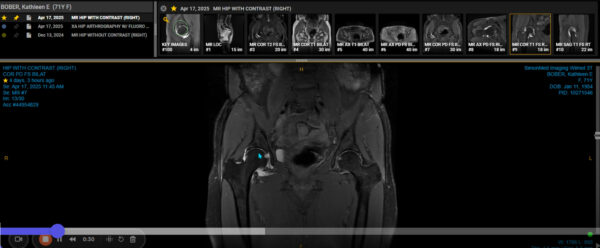

Having tried PRP and stem cell therapy last year for the severe arthritis and degeneration in my right hip with no improvement, I decided to have a total hip replacement. The surgery was done on March 4 by the amazing Dr. Shane Martin, Director, The Joint Replacement Center of Scottsdale, and Founder, Scottsdale Center for Robotic Surgery.